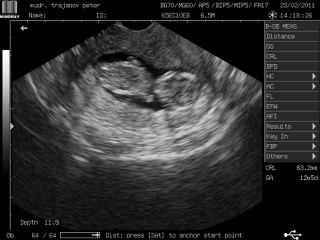

@dzuli08 to je úžasné!!!!! Ja som vždy verila tomu, že zázraky sa dejú.Úplne ťa chápem, že si neprispievala ale si nás len čítala. ja som to tiež robila, ved som na koníku už od r. 2006, od vtedy ako sme sa začali snažiť. A tiež som len čitkala, nechcela som sa deliť s mojimi problemami, robilo mi to ešte horšie, bola som ešte viac skleslá. Takže 3IUI, žiadosť na IVF vypísaná a vám sa podarilo prirodzene 😎 , tak tomu hovorím Božia prozreteľnosť. No a už máte aj srdiečko...juj, teším sa s tebou. A ako sa cítiš? Či tak ako ja, nijako bezpríznakovo?

Aj dnes na kontrolu som mala ísť až v pondelok, ale nevydržala som to. A chodíš ešte na kontroly do Helíku alebo len k svojmu gyn? Ja som sa rozhodla, že ešte v 10 tt tam pôjdem, t.j. za 3 týždne, a možno aj skôr ak dovtedy nevydržím :DD